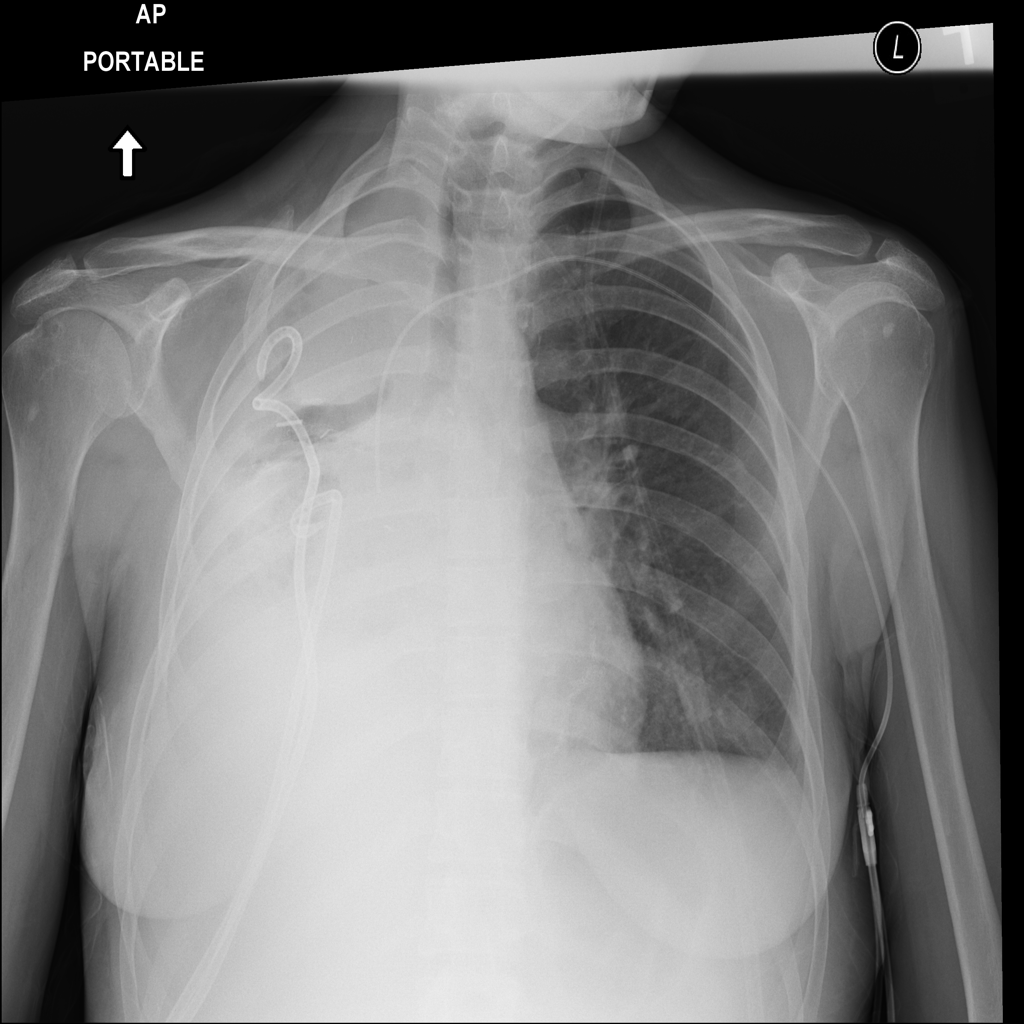

PAT-EBE1 · IMG-019Pneumonia

PAT-EBE1 · IMG-019

AP